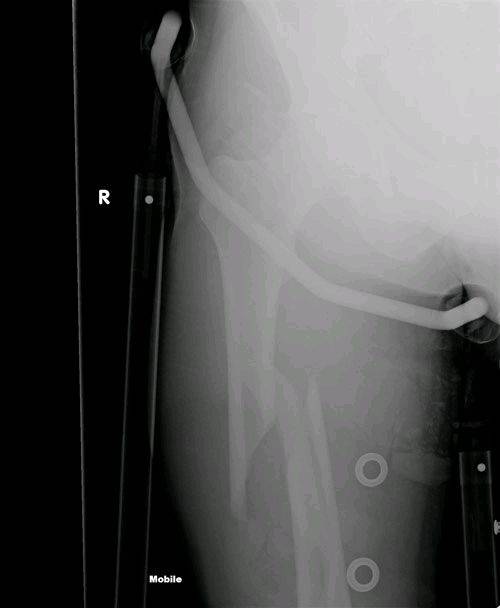

This one took 7 months to heal until I could go kiting again.

I broke my femur 500 meters off the Port Douglas beach 2 years ago.

Strongest pain I experienced so far...

During a jump I came out of one strap and couldn't get out of the other quickly enough. The board acted as an extension of my leg, which snapped into 2 pieces.

Before:

After:

Thats got to hurt. Looks like they needed to brace you before the xray.

I guess you had to drive the windy road to Cairns hospital. I would refuse to go to Mosman with a leg like that.

I was brought to Mossman hospital. They did the first X-Ray there (you are correct with the brace on). Then waiting for the helicopter which didn't arrive because of problems. Then they booked an ambulance. Waiting further in big pain (no morphine at that time either)...